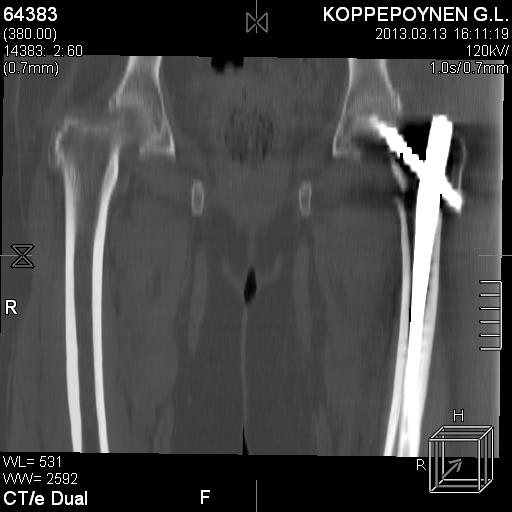

[Ortho] Чрезподвертельный перелом бедра. Остеосинтез стержнем. Перелом металлофиксатора. Дальнейшая тактика?

Делали КТ после операции.